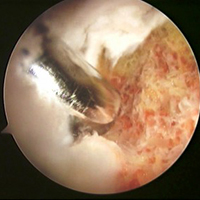

Ortopedi (ARTROSKOPİ)

Shaver Cihazı ve Shaver Uçları

RF Cihazı